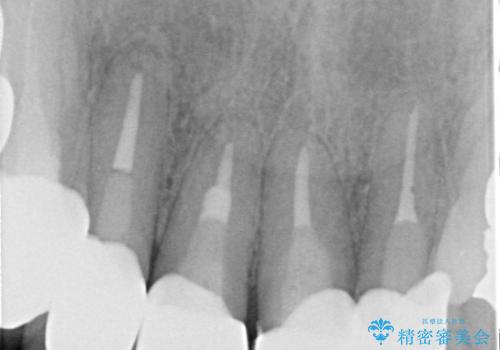

レントゲンを撮影すると、適合不良のかぶせ物が装着されており、根の治療も不十分であることが確認されました。

適合不良のかぶせ物をすべて除去して、根の中の治療から再治療を行うこととなりました。